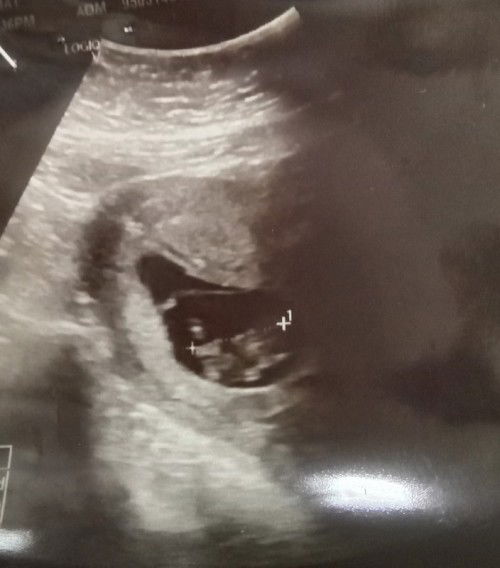

Assalamualaikum semua. I lost my baby malam tadi 8pm.. i share dkt sini for other mommies rujukan and also for my memory. Estimated 6w1d, then yesterday tiba² start heavy bleeding around 5pm+ smpai penuh 1 pad tu. Cramping so bad smpai satu badan shaking lemah. I pergi emergency, doctor scan, masih nampak kantung tpi heartbeat tak jumpa. Doctor suruh rehat dkt rumah, observe smpai bleeding 3 pad penuh, kena masuk balik emergency. I balik rumah, tgh naik lift terus rasa mcm ada ketulan besar keluar drpd bawah. Pergi toilet and nampak laa my little one, pgg dia dlm tangan i. Its so hurtful and scary.. masa tu nangis² sbb terasa sgt kehilangan dia. Baring rehat kejap and around 1230am nk balik hospital utk minta cuci. At 1245am terasa lagi ada yg keluar, this time lagi besar. Tpi yg ni dah x sakit sgt dah, just tak selesa sgt sbb darah² still keluar kan. Lepas nj terus pergi sakit puan dkt hospital putrajaya, they scan utk pastikan kosong, then i tunjuk the kantung² yg keluar, and then they did cervical clearing. Cuci dkt bawah, but this one mmg sakit and tak selesa sbb dia akan buka dari bawah and check manually tisu² balance dan clear betul². Then lepas tu scan balik make sure dah clear dalam, then they inject dkt peha kanan utk kecutkan balik rahim and stop bleeding. Doctor pgg utk 1hr utk observation, bleeding keluar calit² je and sakit semua xde dah cuma sengal² bcos of injection. Then doctor release with ubat tahan sakit and antibiotics. Baby doctor simpan hantar ke labs untik check punca keguguran, blh dpt tahu results after 3months. Ingatkan nak tanam baby tpi xblh dpt balik.. 😔😔 Heart hurts so much sbb kehilangan seorg anak syurga, and this is first baby first time its a scary experience. But womens body is just so strong. So strong and so fragile at the same time.. This time maybe xde rezeki lagi, semua dtng dari allah swt. Insyallah nanti allah bagi baby 🤲 Utk semua mommies, its a scary journey. But exciting jugak. Byk benda kita xthu.. i doakan mommies semua a healthy and happy journey, stay strong selalu. #firsttimemom #firstbaby #anaksyurga